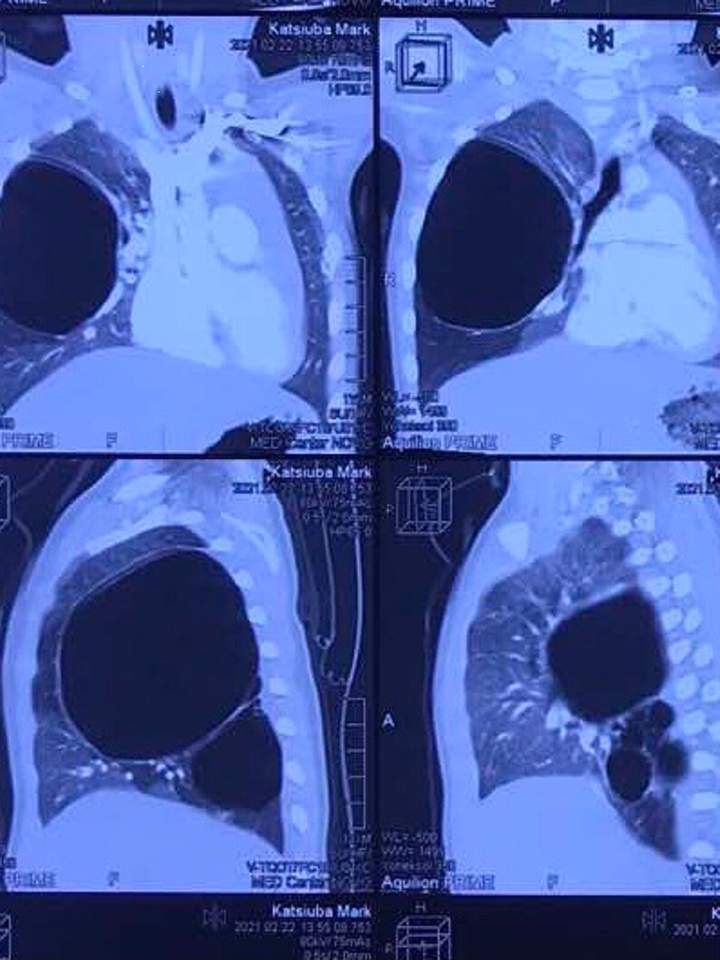

Хоча дивлячись на Марка було важко сказати, що його щось турбує, однак результати обстеження на комп’ютерній томографії показали, що стан дитини критичний. Кіста значно збільшилася, за розмірами вона нагадувала м’яч і зайняла майже всю праву легеню.

Кіста значно збільшилась. Фото: Zaxid.netКіста значно збільшилась. Фото: Zaxid.net

«У хлопчика була вроджена кістозна трансформація правої легені. І коли ми взяли його на операційний стіл, ситуація вже була дуже напружена. Ще трохи і могла статися біда. Кіста роздулася і стиснула здорові частини правої легені, стиснула вона і ліву легеню. За розмірами кіста була як м’яч, вона росла швидше, ніж дитина. Такі кісти можуть тріснути і викликати пневмоторакс. Якби це сталося в селі, могли б і не встигнути», – каже Галина Курило.